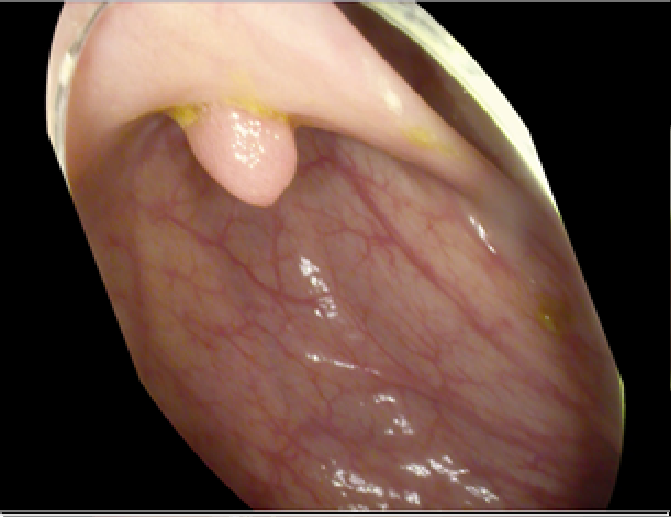

4.1 Dataset Specifications and Augmentation

The study used a publicly available dataset of polyp-frames obtained from the ETIS-Larib database [34], containing 196 polyp images. These images were obtained from 34 different colonoscopy videos of 44 different polyps with various appearances and sizes, having a resolution of 1225×96612259661225\times 966 pixels. The ground truth of polyp areas for polyp datasets is determined by expert video endoscopists. A CNN model trained with such a small amount of data is likely to be meaningless and unstable, so data augmentation was performed on the polyp dataset. Data augmentation had to be performed on the colonoscopy images by considering vivid variations. Otherwise over-fitting would have occurred. In a colonoscopy imagery, polyps exhibits large variations in location, color, and scale. Moreover, variations in brightness and definition also occur due varrying the view-point of the camera. Therefore, in addition to photometric distortions and geometric distortions, we also have considered zooming, shearing, and altering brightness as strategies for data augmentation.

For photometric distortions, we controlled brightness and contrast as an enhancement, while blurring by adding noise with a standard deviation (σ)𝜎(\sigma) of 1.0. Similarly, for geometric distortions, clock-wise rotation of the polyp images with angles of 90°90°, 180°180°, and 270°270° were performed. Zoom-in and zoom-out with zooming parameters such as 30.00% and 10.00% were performed to obtain different scales of polyp images. Lastly, shearing for both the x-axis and the y-axis was performed to shear the images from left to right and top to bottom, respectively. Fig. 4 shows photometric and geometric forms of image augmentation. In this way, we augmented the data set of the ETIS-Larib database from 196 polyp images to 2,156 images, which is more suitable for training the proposed deep CNN model.